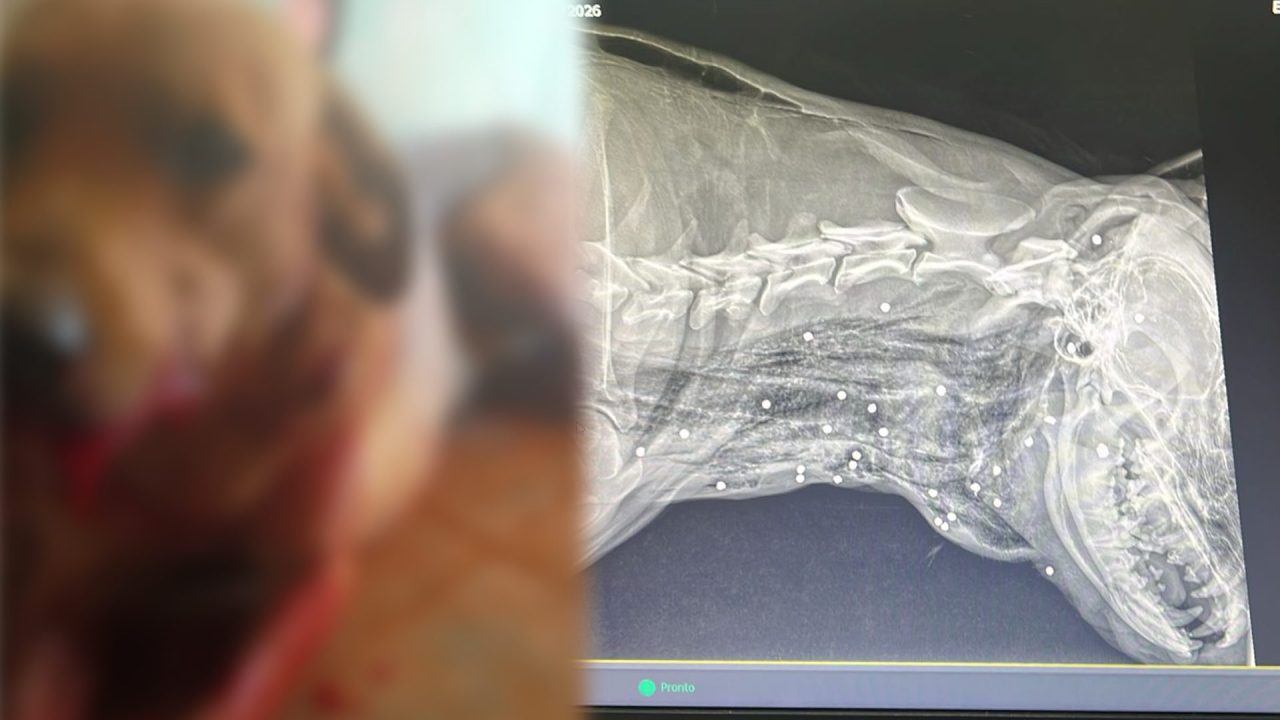

Segundo a tutora, o animal foi encontrado gravemente ferido e com sangramento intenso. O verificarem o que havia ocorrido, notaram diversos ferimentos, possivelmente causados por munições calibre .12.

O autor dos disparos não foi localizado e não há testemunhas. O cão, de nome Billy, permanece internado em uma clínica veterinária de Limeira. Ele está se recuperando e a princípio, passa bem.